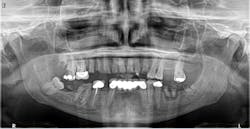

When a new patient presents to my practice for an initial oral examination, I usually obtain a 2-D or 3-D image, depending on what he or she requires in terms of treatment. In other words, if a routine new patient presents to the practice, then we obtain a 2-D panoramic image. Due to its low dose and simplicity, digital 2-D panoramic imaging remains an indispensable tool for the majority of dental practices. And whether you are a general practitioner or a specialist, a compact multifunction system with multiple fields of view can cover all your routine panoramic needs (figure 3).

Figure 3: An example of a panoramic image produced by a CBCT system